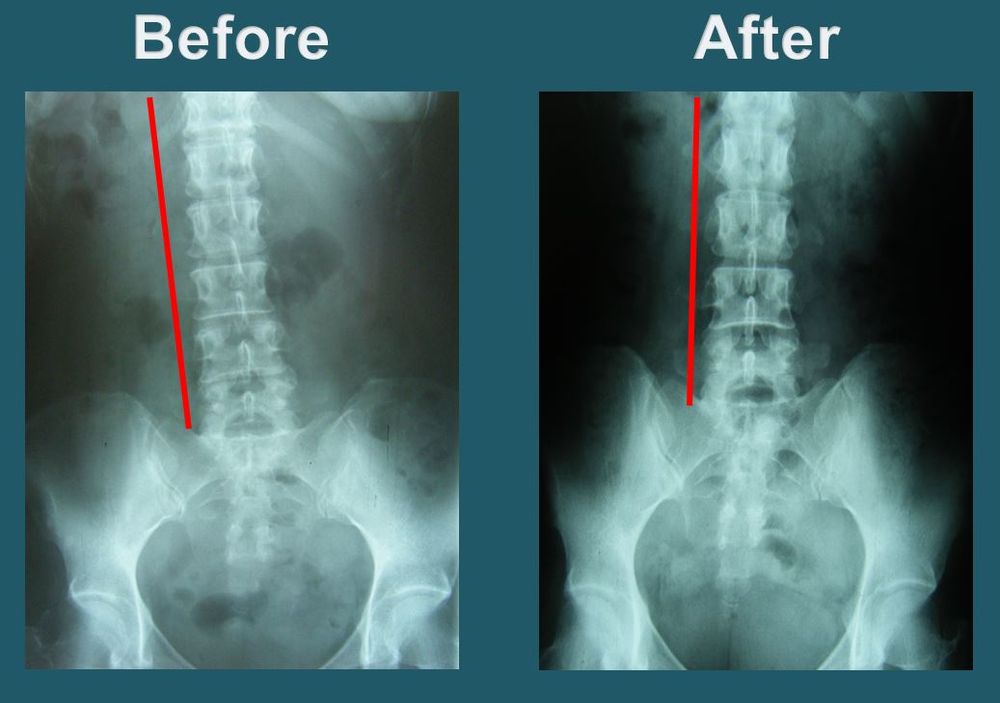

Dr. Park will take X-rays of the upper cervical region, neck, full spine, and pelvis to observe and examine the degree of misalignment. The doctor will then implement the procedure to restore head, neck and spinal alignment. This procedure is performed by the doctor’s own hands, without the use of any needles or electric therapy.

As soon as the vertebrae is aligned correctly, the brain will immediately start sending healing messages to those parts of the body affected by the misalignment and begin the natural self-healing process. Blockage of brain to body messages can be the direct or indirect cause of most health problems. On each visit, Dr. Park seeks to regain and maintain the proper alignment of the spine, aiding each patient through the process of recovery and healing.